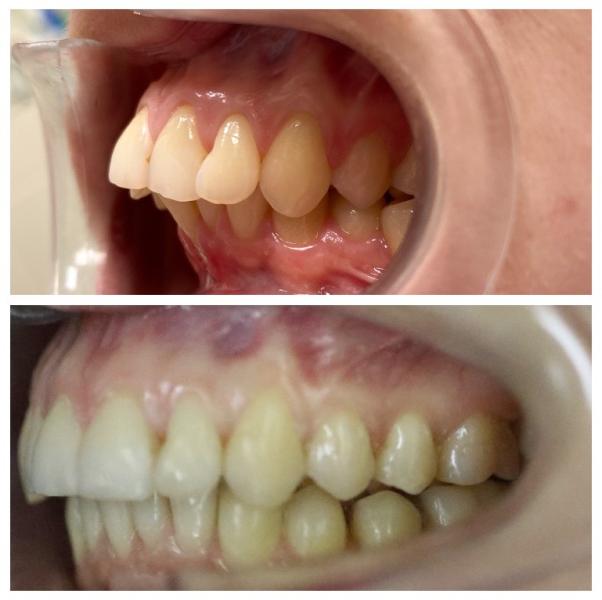

Как я исправила прикус за 2 года? История с элайнерами

Делюсь сложным кейсом лечения на элайнерах длиной в 2 года и 1 месяц.

Потребовалось удаление всех восьмерок и терпение пациента к улыбке своей мечты. Мы очень довольны результатом.